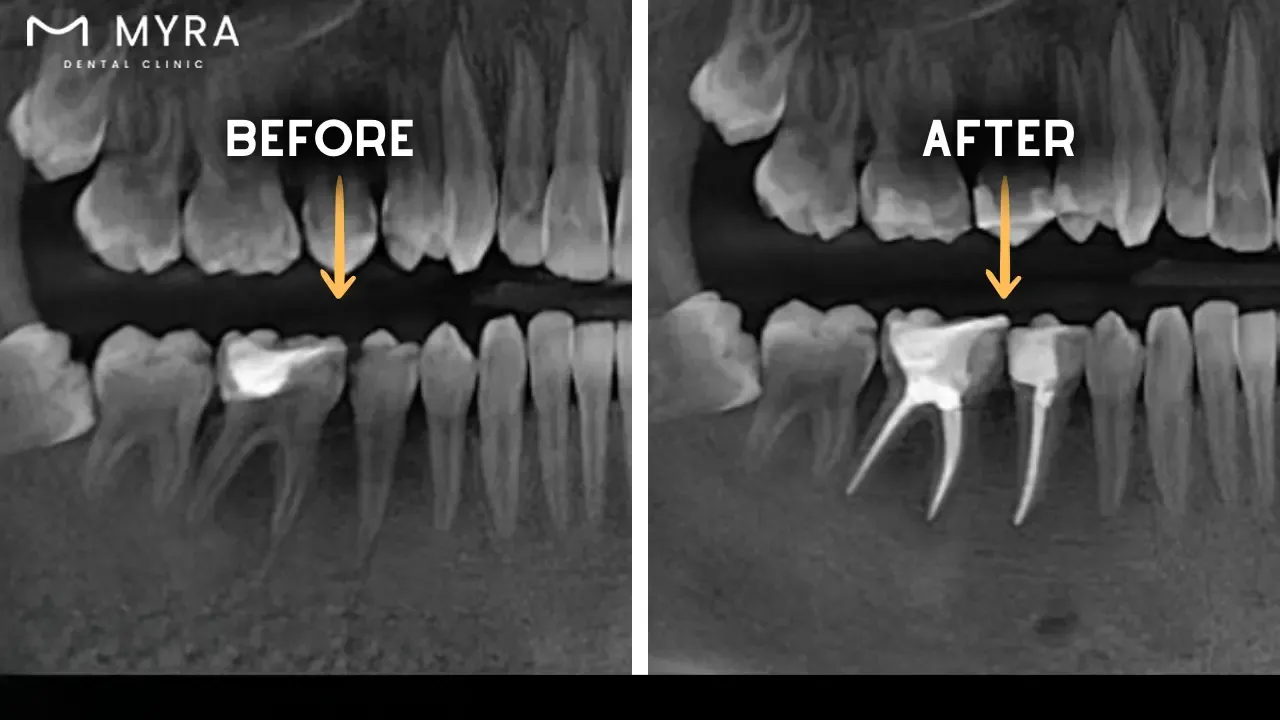

Get the “imaging,” which is crucial in dentistry, especially endodontics. Modern techniques, including digital radiography and cone beam 3D technology, allow patients to see what is happening inside teeth.

Endodontic retreatment involves the endodontist reopening the tooth, removing the previous filling materials, thoroughly cleaning and reshaping the canals, and refilling and sealing them to encourage healthy healing and retain the natural tooth. The treatment is intended to maintain good oral health for a long time. The endodontist explains different treatment choices, including retreatment, which entails reopening the tooth to obtain root canal filling material. The endodontist cleans the canals and inspects the inside for additional canals or abnormal morphology. Endodontic surgery is recommended if the canals are small or clogged. A new crown or restoration is implanted after retreatment to safeguard and restore the tooth's functionality.